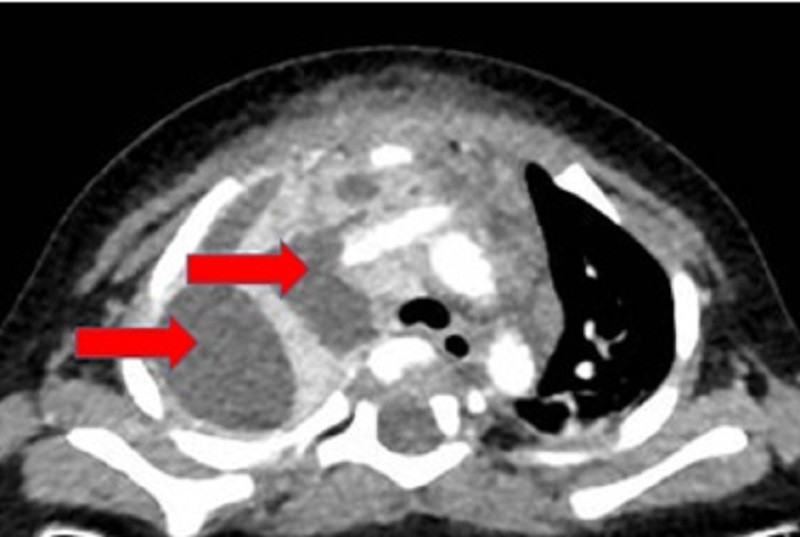

BS Nguyễn Minh Tiến, Phó giám đốc Bệnh viện Nhi Đồng Thành phố cho biết, thời điểm nhập viện, bệnh nhi sốt cao, lừ đừ. Kết quả siêu âm ghi nhận, bé K. bị áp xe dưới da vùng hàm và thành ngực. Kết quả CT-Scan ngực có tiêm thuốc cản quang cho thấy khối tổn thương kích thước lớn, lan rộng từ vùng cổ xuống trung thất, tạo ổ áp xe trong lồng ngực vùng trung thất với nhiều hạch gây hoại tử viêm xẹp đáy phổi hai bên.

| CT-Scan ngực cho thấy khối áp xe rất lớn ở vùng trung thất màng phổi bên phải (ảnh: BVCC) |